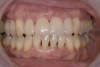

Fig. 10  The postoperative situation: anterior view.

Figure 10

Fig. 11  The postoperative situation: left lateral view.

Figure 11`

Fig. 12  The postoperative situation: right lateral view. Clinical work and photographs by Dr. Markus Blatz, dental technology by Michael Bergler, MDT.

Figure 12

High-strength ceramic materials can be used in select cases to fabricate resin-bonded bridges to replace missing teeth as an alternative to removable prostheses or more invasive procedures such as conventional bridges or dental implants. The two missing lower central incisors (Figure 6) were replaced with two zirconia-based resin-bonded bridges (Figure 7). The single-retainer wing design has shown more than 94% clinical success after 10 years, which is significantly higher than the conventional two-retainer design (67.3% success).6 Proper bonding, however, is key for success and employs an air-particle abrasion step (Figure 8) followed by the application of a special ceramic primer (Figure 9). Figure 10 through Figure 12 demonstrate the clinical outcome.